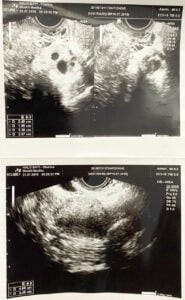

Inilah hasil usgnya, Pada saat itu, biaya untuk menjalani pemeriksaan USG transvaginal cukup terjangkau, hanya 200 ribu rupiah.

Tapi tiba-tiba, saya cek hasil pemeriksaan yang menyebutkan dugaan PCOS dan vaginismus. Bingung, euy…